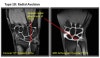

Type 1 tears are called traumatic tears. Falling on an outstretched hand and excessive arm rotation are the most common causes.

Type 2 TFCC tears are degenerative or chronic. They can occur over time and with age. The degenerative process wears the cartilage down over time. Some inflammatory disorders, such as rheumatoid arthritis or gout, may also contribute to Type 2 TFCC tears.

* Central : Poor vascularized(Healing potential minimal)

Arthroscopic debridement up to 2/3 of articular disc